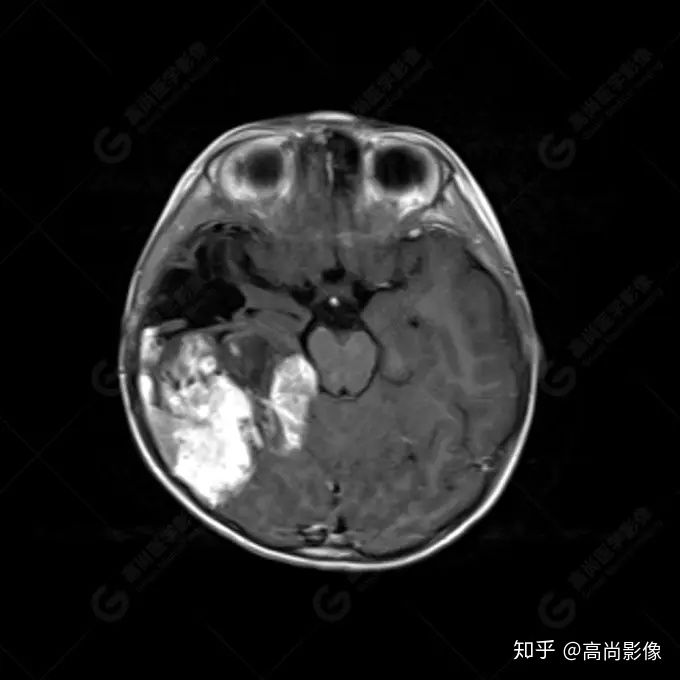

右側(cè)顳葉腫瘤切除術(shù)后(具體不詳):右側(cè)顳部骨質(zhì)不連續(xù)呈術(shù)后改變,右側(cè)顳葉術(shù)區(qū)見片狀長(zhǎng)T1長(zhǎng)T2信號(hào)影,F(xiàn)LAIR呈低信號(hào);術(shù)區(qū)后方右側(cè)顳枕葉見一巨大占位性病變影,邊界欠清,大小約6.2×5.8×4.3cm(前后×左右×上下),信號(hào)不均勻,T1WI呈等稍低信號(hào)間雜少許高信號(hào),T2WI呈高稍低混雜信號(hào),DWI示部分病灶彌散受限,相應(yīng)ADC圖減低,磁敏感序列見部分呈極低信號(hào),增強(qiáng)掃描可見明顯不均勻強(qiáng)化,鄰近硬腦膜及小腦幕增厚并明顯強(qiáng)化;另延髓右前方及右側(cè)橋小腦角區(qū)見一不規(guī)則形異常信號(hào)影,大小約3.2×1.3×3.7cm(左右×前后×上下),呈長(zhǎng)T1稍長(zhǎng)T2信號(hào),F(xiàn)LAIR呈等信號(hào),DWI未見受限,增強(qiáng)后明顯均勻強(qiáng)化,鄰近腦膜明顯強(qiáng)化。鄰近腦實(shí)質(zhì)及右側(cè)顳角明顯受壓;左側(cè)大腦半球未見局灶性信號(hào)異常,中線結(jié)構(gòu)稍左移。

右側(cè)顳葉腫瘤切除術(shù)后:現(xiàn)術(shù)區(qū)后方右側(cè)顳枕葉及延髓右前方占位,右側(cè)顳枕部硬腦膜及小腦幕明顯強(qiáng)化,結(jié)合既往影像資料,考慮為胚胎源性惡性腫瘤,如非典型畸胎樣/橫紋肌樣瘤(AT/RT)或原始神經(jīng)外胚層腫瘤(PNET)。